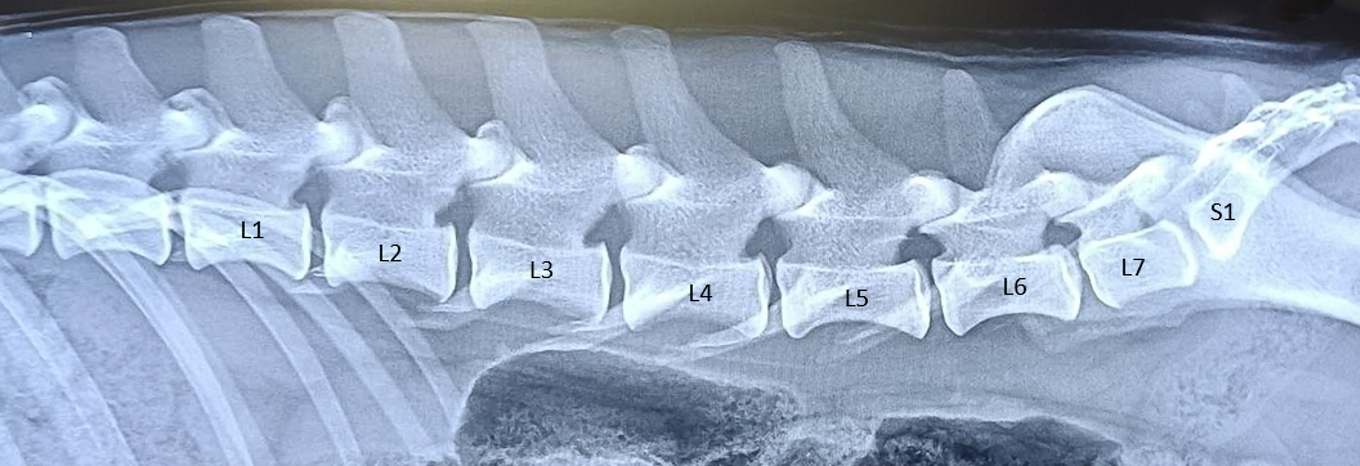

Övergångskotor förekommer troligen hos alla två- och fyrfota ryggradsdjur med bäcken. Hundar ska ha 7 ländkotor men kan ha både 6 och 8 stycken.

När det inte finns 7 fullständigt normala kotor och en normal övergång till bäckenet talar man om övergångskotor. En övergångskota är alltså en missbildning. Missbildningen kan vara minimal och betydelselös för hunden men också, i svåra fall, vara handikappande. Ärftliga faktorer anses ligga bakom en del av problemen. Hur vanligt förekommande avvikelser är hos Bretoner i Sverige och hur det påverkar hälsan återstår att se.

I väntan på att vi har en modell för Svenska Bretonklubben, uppmuntrar vi alla Medlemmar att i samband med HD-röntgen frivilligt även utföra en ryggröntgen för att öka kunskapen om frekvensen av LTV hos Bretoner. Minst 3 olika röntgenbilder behövs,

- Lateral bröstrygg

- Lateral ländrygg

- Ventrodorsal projektion av korsbenet och minst 2 av de flesta svanskotorna i ländryggen